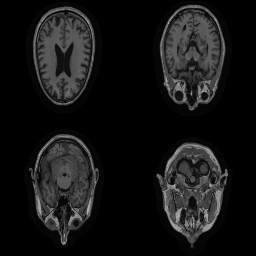

| Original | Renderings after de-identification | Original | MRI slices after de-identification | ||||||

| CP-GAN | FACE MASK | DEFACE | QUICKSHEAR | CP-GAN | FACE MASK | DEFACE | QUICKSHEAR | ||

Benchmark De-Identification Methods. We compare our result with three publicly available and widely-established methods for de-identification of MRI head scans, depicted in Figure 3. All methods have in common that they (1) are not deep-learning-driven, (2) require no additional training and (3), are used on a day-to-day basis in neuroscience and clinical research. All procedures were applied with default settings on images of resolution . The methods include QUICKSHEAR [Schimke et al.(2011)Schimke, Kuehler, and Hale], FACE MASK [Milchenko and Marcus(2013)], and DEFACE [Bischoff-Grethe et al.(2007)Bischoff-Grethe, Ozyurt, Busa, Quinn, Fennema-Notestine, Clark, Morris, Bondi, Jernigan, Dale, Brown, and Fischl]. Descriptions of the methods are provided in the Appendix. We also include MRI WATERSHED [Ségonne et al.(2004)Ségonne, Dale, Busa, Glessner, Salat, Hahn, and Fischl], a skull-stripping method that removes everything except the brain.